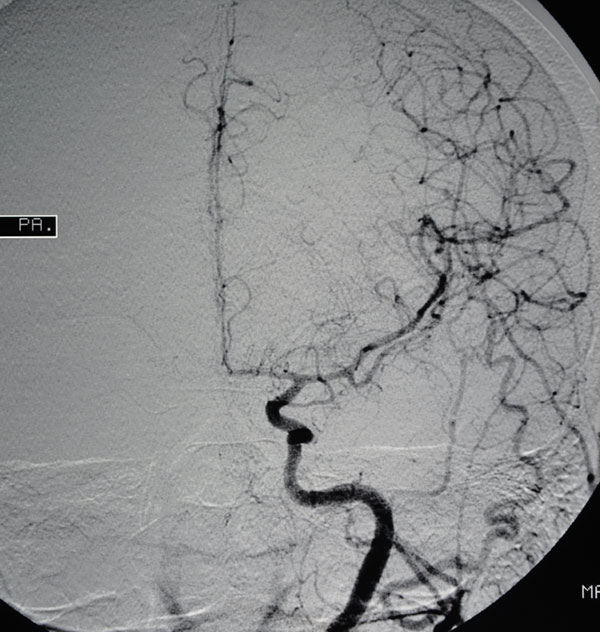

4. Angiography

In a small number of patients with skull base problems, formal angiography of the blood vessels in the brain may prove useful. This is particularly so for patients with glomus jugulare tumours. This entails injecting dye directly into the blood vessels of the brain. Access is obtained through an artery in your groin and catheters are then fed up into the large vessels in your neck from where the dye can be injected. It usually entails a day case admission and will be carried out by an expert neuroradiologist who is skilled in performing cerebral angiography and this is part of the highly skilled team with which the Brain and Spine Clinic works.